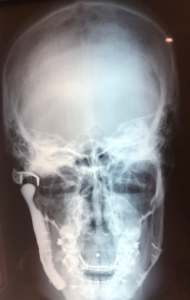

Figura 4. Imagen frontal de control radiológico demostrando la simetría esquelética conseguida con el tratamiento personalizado.